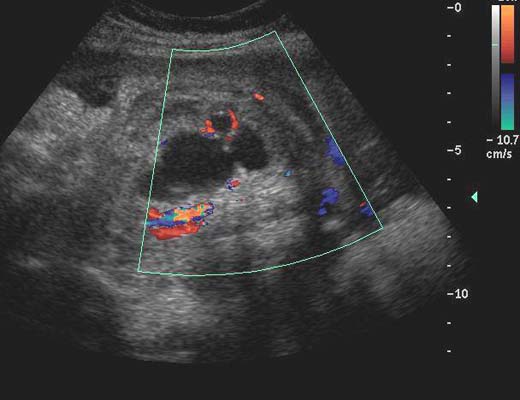

Anéchogène ovalaire